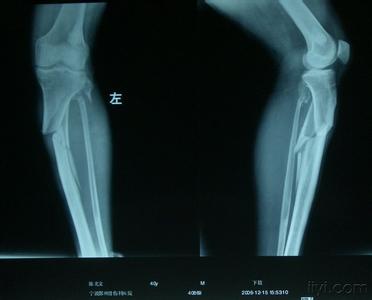

刚刚得到消息说,博古特经过 X 光检查,确定博古特的伤势是左腿胫骨骨折,但是骑士还没公布他的休战时间有多长。

胫骨是小腿上那根粗的骨头,是支持小题的主要骨头,也是连接大腿的骨头,这根骨头骨折少说要一、二个月的治疗,看样子博古特赛季是要报销了。